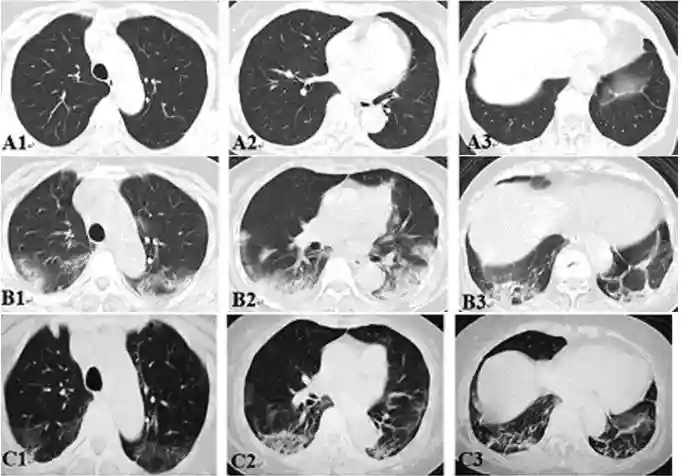

结果患者在接受细胞治疗期间仍然维持常规治疗方案,未出现与细胞治疗相关的不良反应,见图1、表1。干细胞治疗期间,患者的淋巴细胞数量不断回升,尤其是T细胞计数(包括CD4+T细胞和CD8+T细胞)明显回升直至正常水平,NK细胞和B细胞计数也持续回升;与之相对应的是,中性粒细胞/淋巴细胞比值持续下降,主要的炎症因子IL-6和CRP水平持续下降,见图2。干细胞治疗后患者肺部炎症反应明显减轻,见图3。

图3:患者治疗前后肺部CT

(3)上述作用为中性粒细胞的下降和淋巴细胞的增殖提供了良好的环境。这些效果与抗病毒药物或者提升淋巴细胞数量和功能的药物联用,为最终清除病毒提供了帮助。此外,除了IL-6,笔者发现患者血液中的IL-2、IL-4、IL-10、TNF-α和IFN-γ等因子并无明显的升高。从笔者的结果中也可以看出,相对于单一种类的细胞计数,中性粒细胞/淋巴细胞的比值可能是反映新冠肺炎患者炎症状况的更好指标,这与其他课题组的报道基本一致。从CT影像的结果也可以看出,单纯的使用抗病毒药物对于迅速改善肺部的炎症效果不是特别理想,需要与脐带间充质干细胞输注等损伤修复的疗法进行联合。